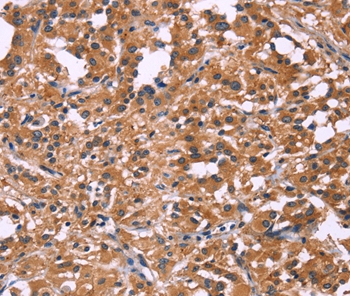

Immunohistochemical analysis of paraffin-embedded Human thyroid cancer tissue using #35713 at dilution 1/20.

Immunohistochemical analysis of paraffin-embedded Human liver cancer tissue using #35713 at dilution 1/20.